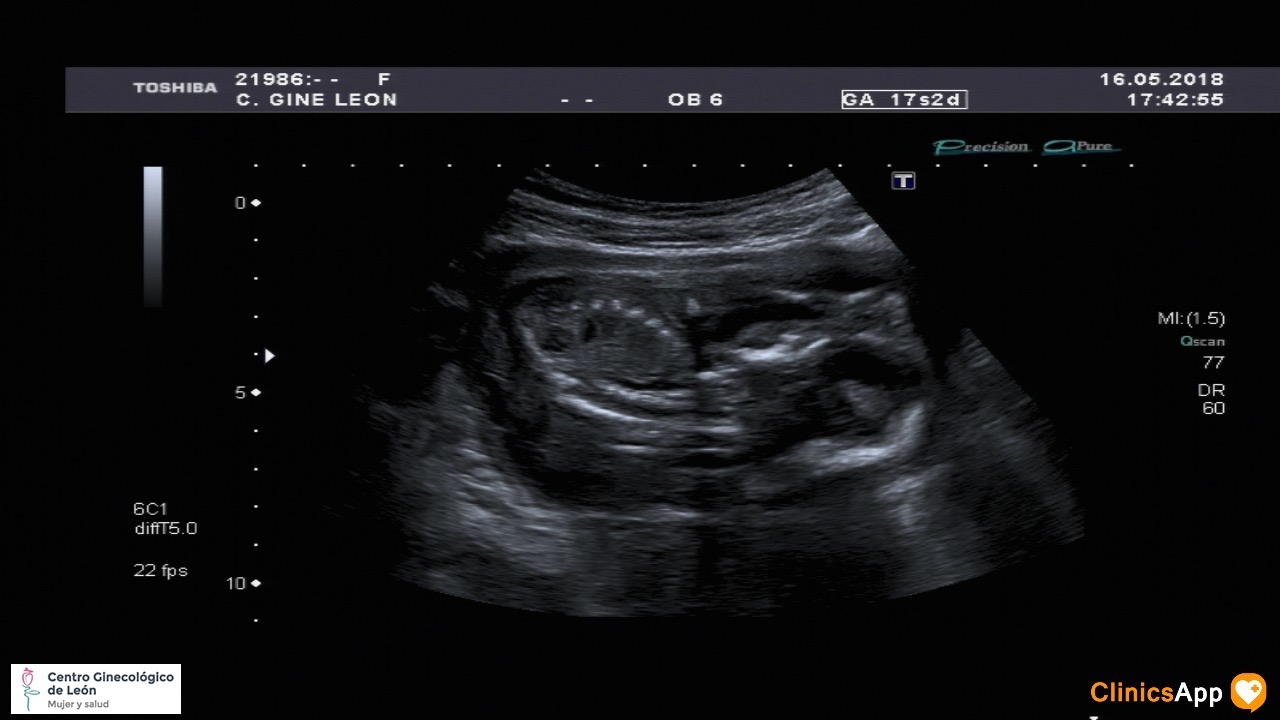

Ecografías de hoy